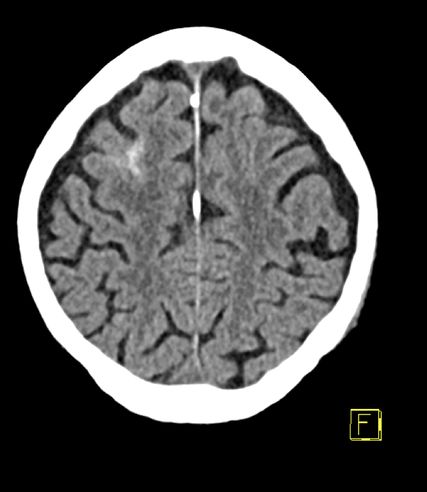

Abb. 2: Unauffälliges CCT einer 82-jährigen Patientin mit einer Schädelprellung unter der Einnahme von Edoxaban (Lixiana®)

Bemerkenswert ist, dass bei der oben erwähnten Patientengruppe in der Diagnostik nahezu ausnahmslos an der kranialen Computertomografie (CCT) (Abb.2) festgehalten wird. Diese radiologische Abklärung ist aus Sicht der aktuellen Literatur zu hinterfragen und zu reevaluieren.9,12 Selbst Colas et al. stellten in ihrer Arbeit die Frage nach dem Benefit einer standardisierten Computertomografie bei Patient*innen mit leichtem SHT, da sie ein gleiches Outcome bei Patient*innen mit und ohne eine in der CCT detektierte intrakranielle Blutung und Einnahme einer antithrombotischen Therapie feststellten.13